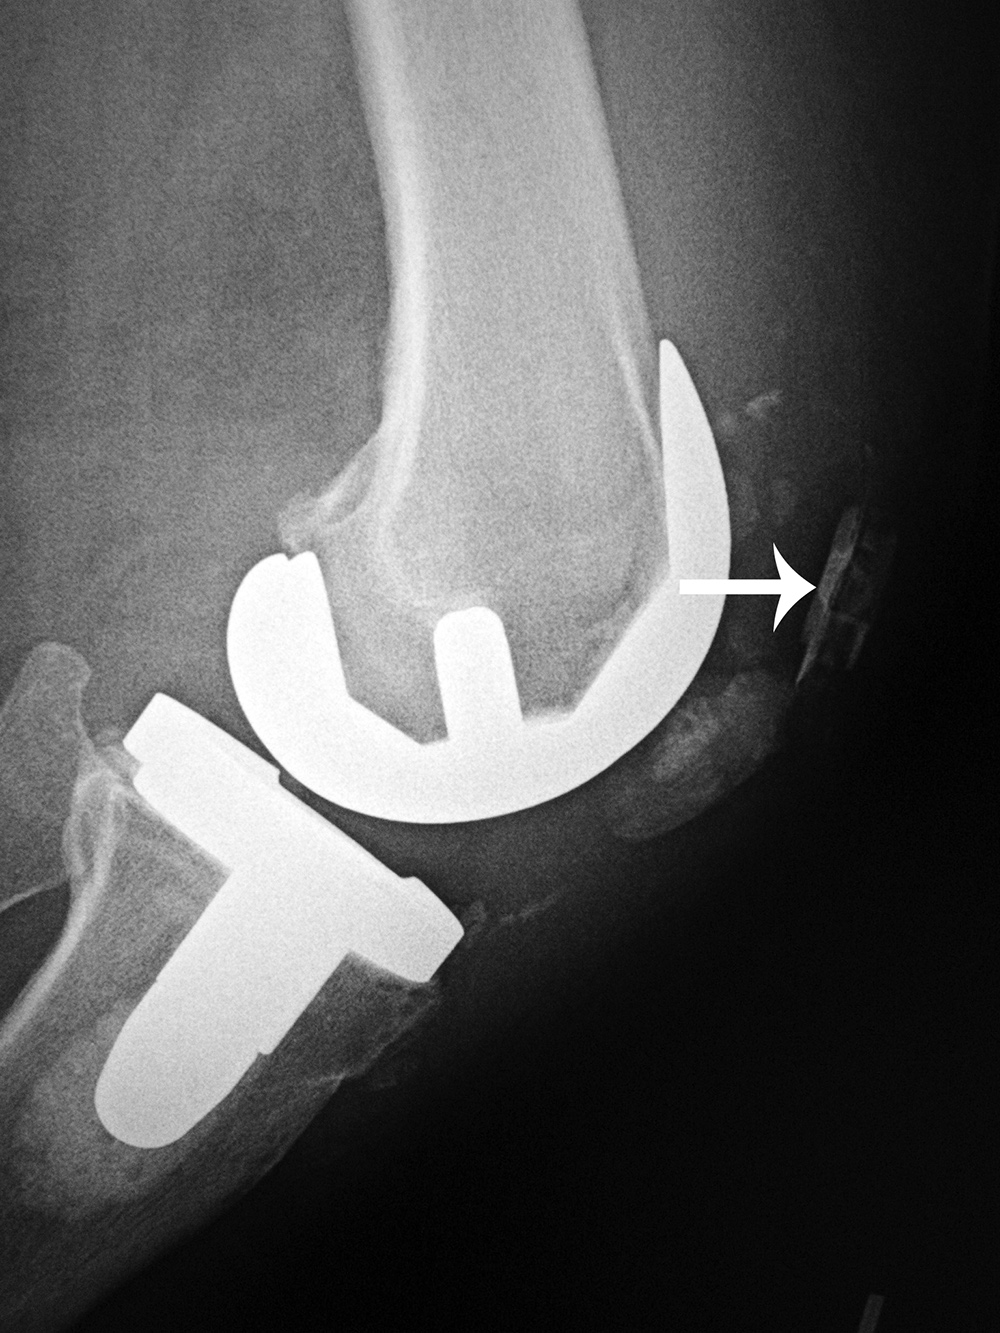

Left total knee prosthesis patellar button dislocation |

The patellar button is dislocated superiorly (arrow). |